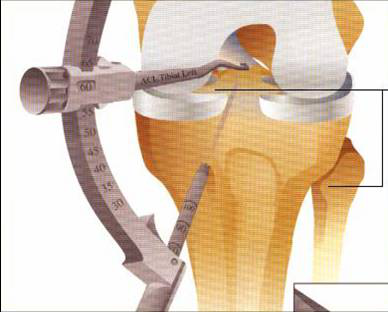

脛骨點(diǎn)選取

股骨點(diǎn)